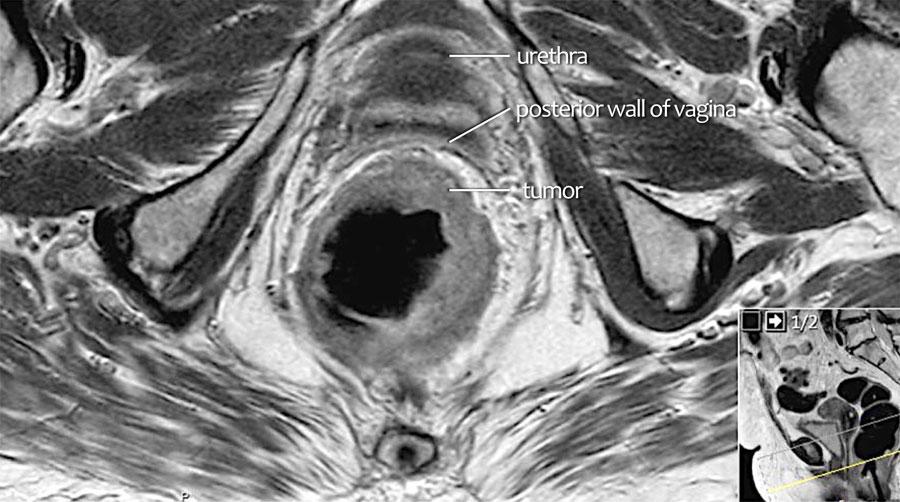

Ví dụ

Cuộn qua các hình ảnh.

Trên MRI trục ngang, tín hiệu khối u trung gian lan vào thành âm đạo sau (mũi tên) cho thấy xâm lấn T4b.